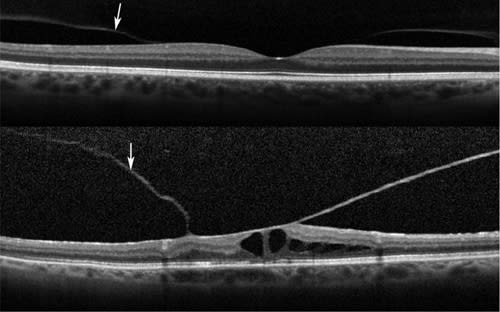

Ultrasonography also may be useful in confirming the presence of PVD. As seen in the top image of Figure 5, an SD-OCT scan focused on the retina/optic nerve head shows no vitreous attachment. The bottom image shows the posterior hyaloid on SD-OCT when the Weiss ring was focused.

Figure 5. Simultaneous SLO/SD-OCT scans of optic nerve head.

Top: Focus is on the optic disc/retina showing normal optic disc with no vitreous attachment on the optic nerve head margins. Weiss ring is seen in infrared image.

Bottom: Focus moved anteriorly on the Weiss ring, showing detached posterior hyaloid on SD-OCT scan. Determination of complete PVD is important for making decisions for laser for symptomatic lattice degeneration and may also be useful in planning certain types of surgical procedures.